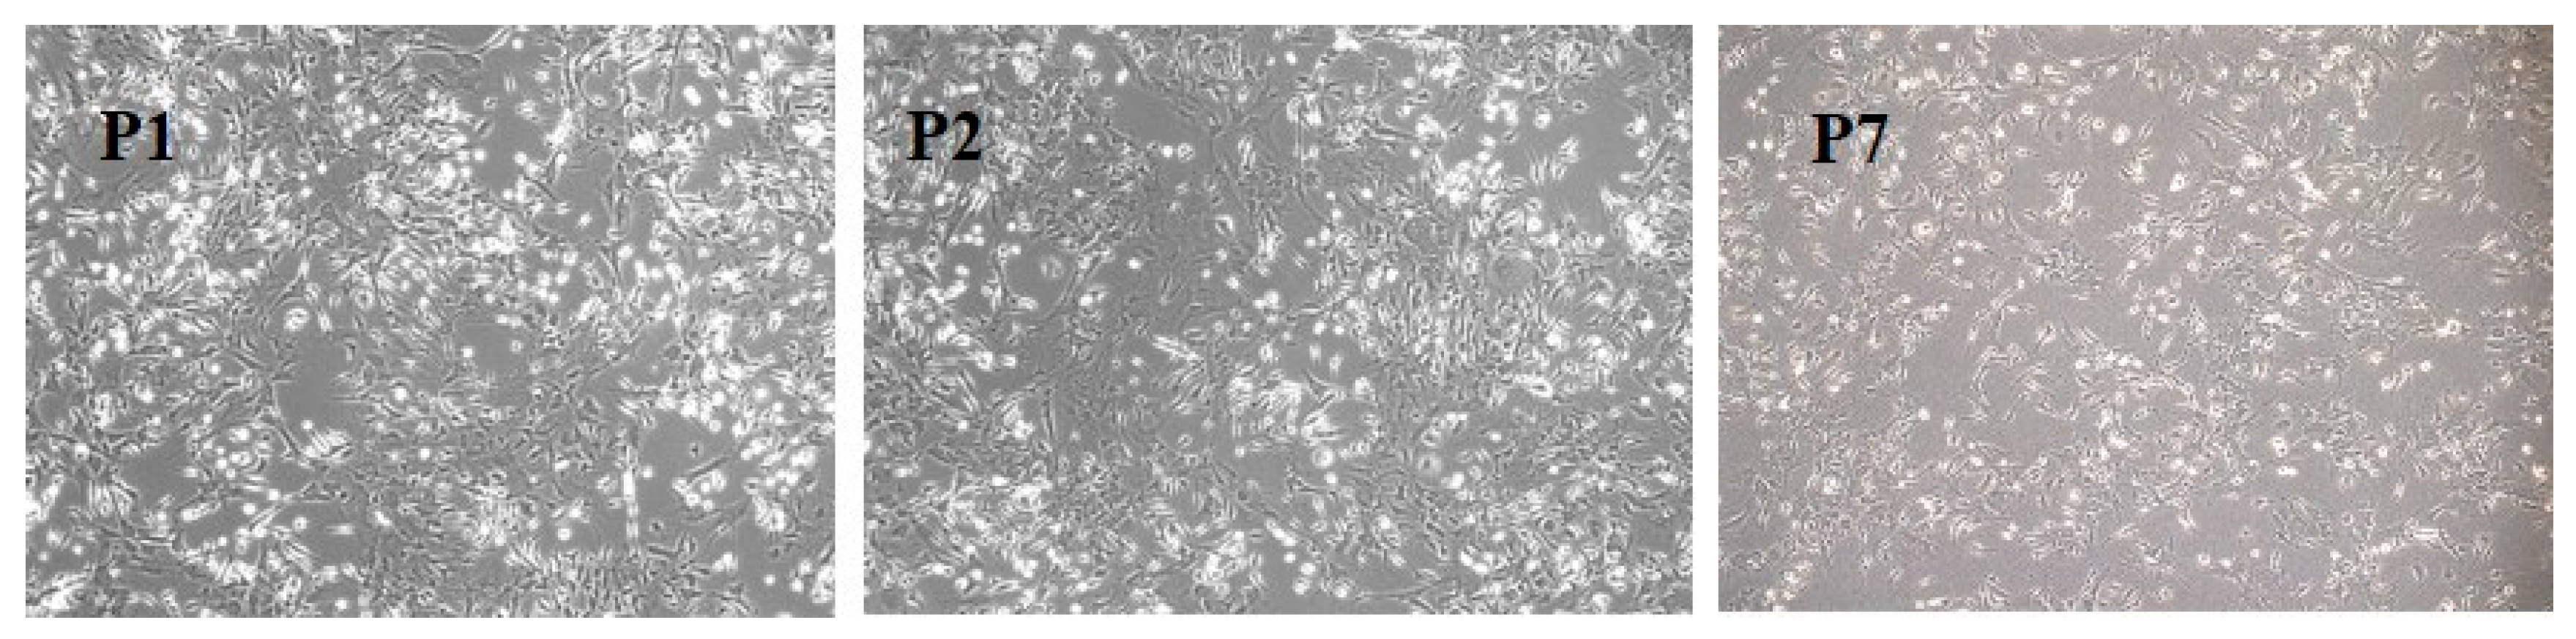

3.1. BM-MSC Culture

3.2. BM-MSC Characterization